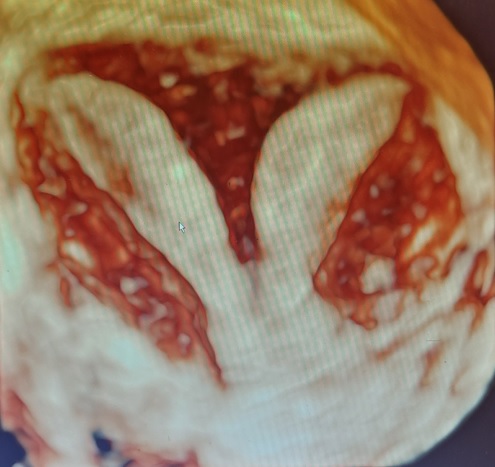

▲胚胎植入右側子宮腔的位置 ▲胎兒在產婦右側子宮腔內著床發育

因著求子心切,加上政府推出擴大試管補助方案,讓陳小姐和先生決定直接採用試管療程,不想再浪費時間嘗試自然受孕,希望能儘快抱到孩子。於是,李茂盛院長幫王小姐進行1次取卵手術共取出9顆卵子,在受精後得到3顆囊胚,經過「AI人工智慧試管技術」、「胚胎影像即時監控系統(T/L)」,從中找出發育最好的1顆第5天囊胚,植入右側的子宮腔內,囊胚即順利著床發育,直到孕期34週又2天時,陳小姐自然產下重達2460公克的健康男寶。